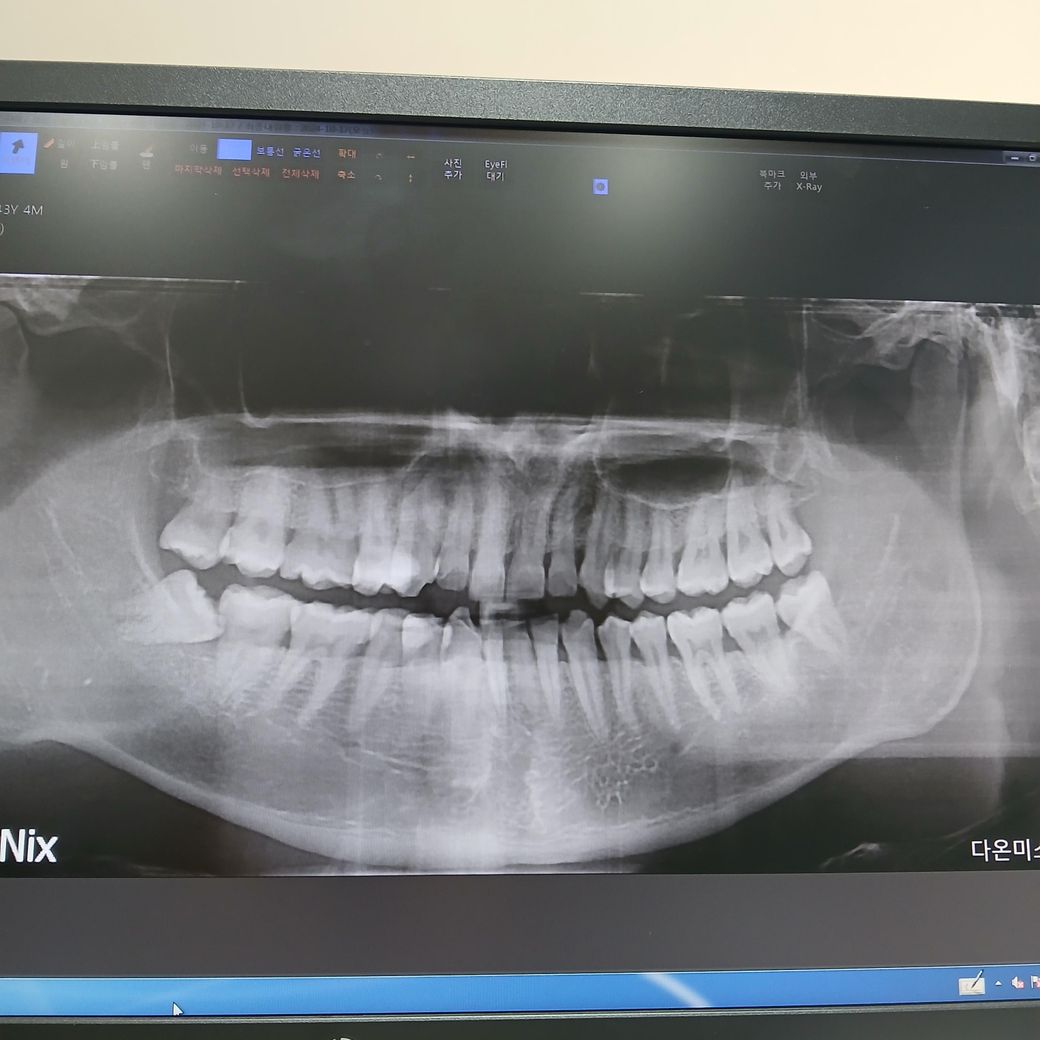

엑스레이 상으로 치아가 겹쳐 보여서 충치가 자세히 보이진 않지만, 과잉치가 저정도 충치가 잇다면 아마 주변치아들도 충치가 상당히 진행되엇을것으로 판단됩니다.